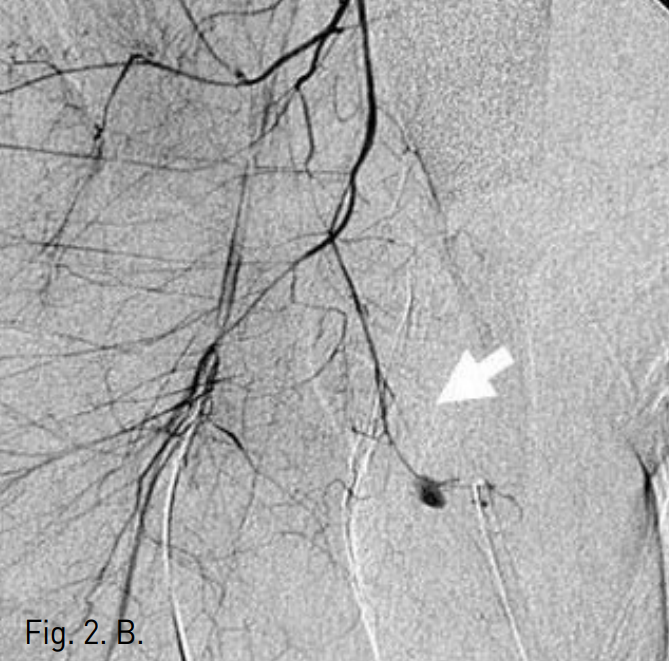

To identify the location of the bleeding site, digital subtraction angiography was performed. Selective angiogram of right common iliac artery showed two contrast extravasations or bleeding points at suprapubic area(Fig. 2A). Selective internal iliac arteriogram showed only one bleeding point from the obturator artery(Fig. 2B). After superselective cannulating into the feeding branch from the obturator artery by using a coaxial microcatheter, embolization was performed with gelfoam particles(Fig. 2C). Follow-up right common iliac angiogram showed persistent contrast extravasation and identified feeding branch of aberrant obturator artery from the inferior epigastric artery(Fig. 2D). Additional selective embolization was performed with gelfoam particles.

B. Internal iliac arteriogram shows active bleeding from the obturator artery (arrow).